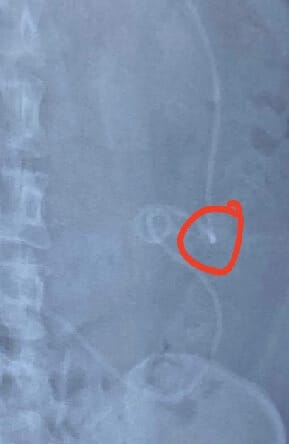

Shunts, a bone of contention for many people diagnosed with Hydrocephalus. I would almost go so far as to say there’s a divide on the feeling towards this “lifesaving” device. Not everyone feels the love when it comes to them, but we all know that without them, things would...